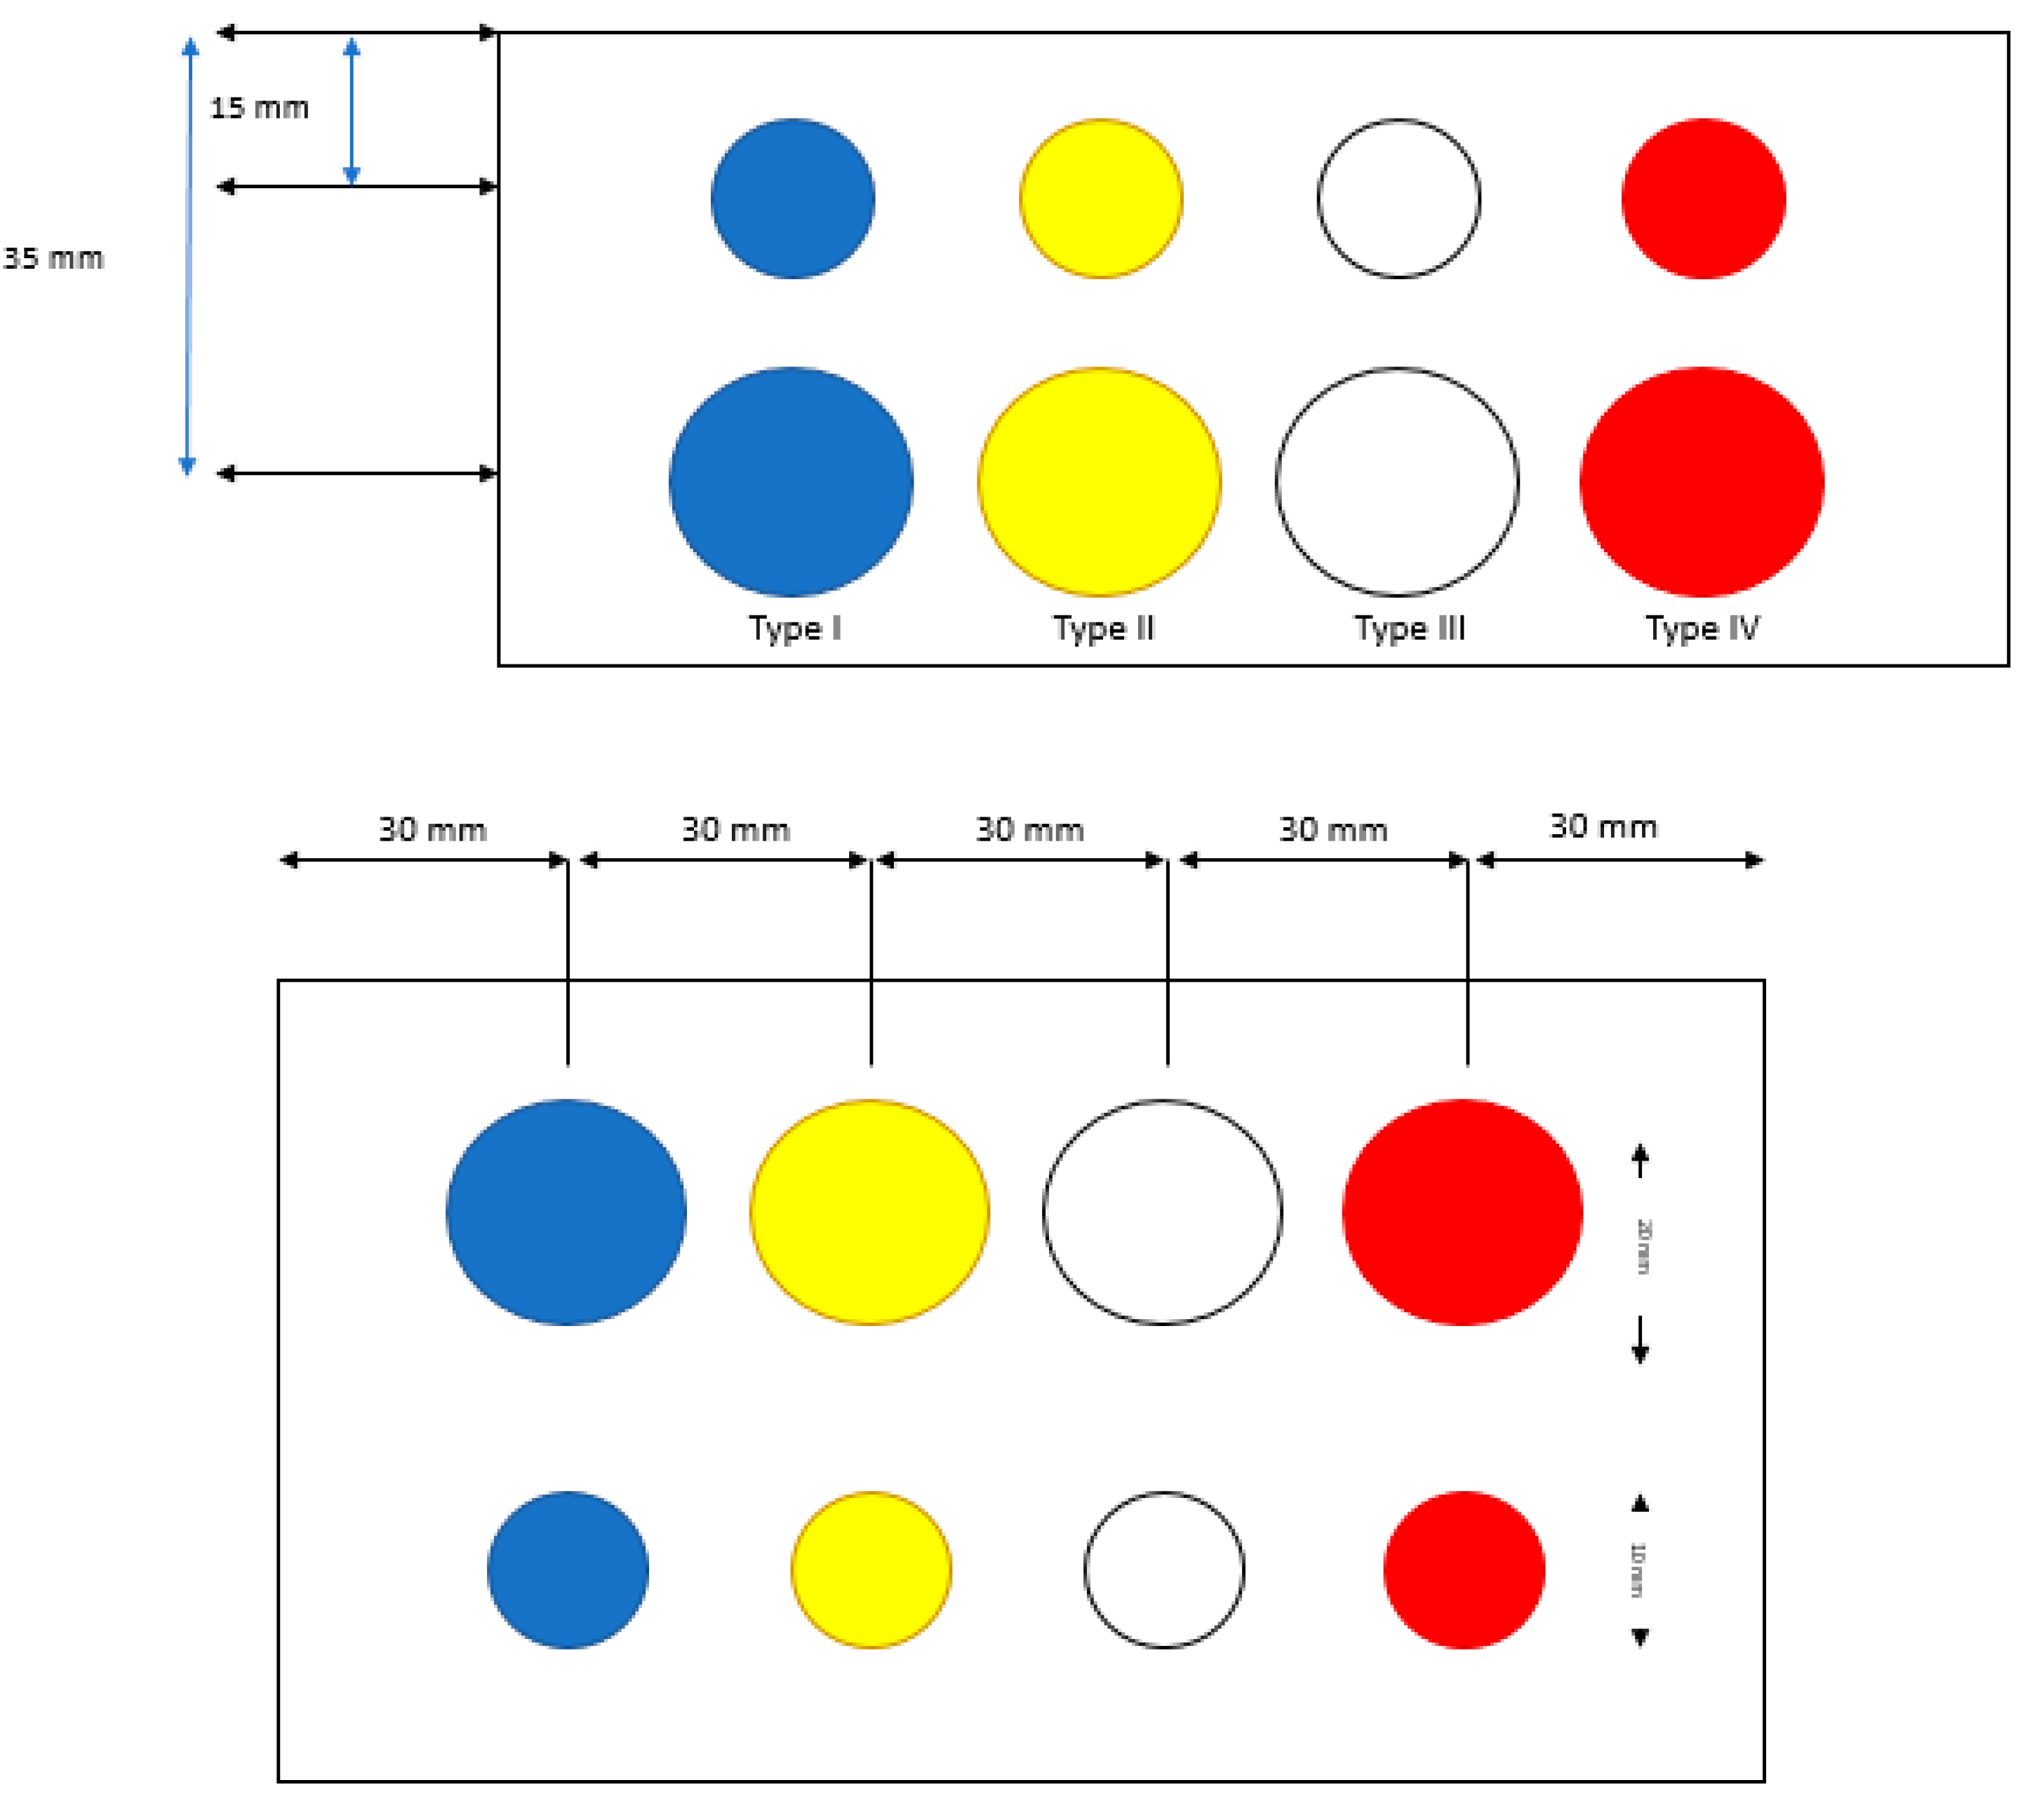

2.2. Ultrasonic-Based Elastography Phantoms

3.1. Robustness Evaluation Regarding Size and Type of Inclusions